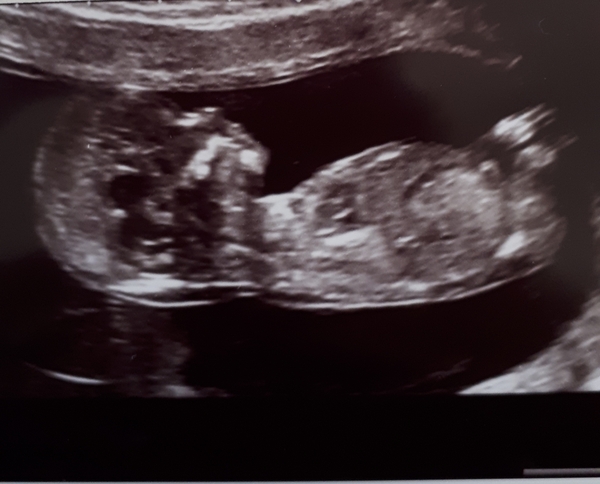

Hi and Thanks @december2019 yeah they will be over the moon either way but I've told them it's most likely a boy....Will post my inbetween the legs scan pic,me and the sonographer had a giggle as could see the boy parts! we've already got 2 boys and their 12wk scans was just as telling! lol

December 2019-Thread 2

@lovebeingmum9 yesss deffo looks like a little boy there haha

@lovebeingmum9 I’m so bad at anatomy! I can see a rabbit with an unhappy face